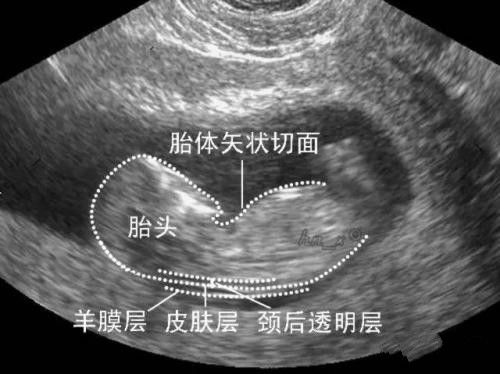

NT是英文单词nuchal translucency的缩写,中文翻译过来就是胎儿的颈项透明层厚度,指胎儿颈后皮下组织内液体积聚的厚度,反映在超声声像图上,即为胎儿颈椎水平矢状切面上测量颈后皮肤至皮下软组织之间无回声层的最大厚度。

最佳孕周是孕11-13+6周,胎儿头臀长在45-84mm之间测量NT才有意义。要求胎儿正中矢状切面,颈部自然姿势,尽可能放大头部及上胸,正确放置游标尺,在距离最阔的透明地带量度。应测量最少三次,并记录测量所得的最大数值。近年来,全国地区举办过多次NT测量培训班,已有越来越多的医师掌握了这项技术,杭州市第一人民医院超声影像科医生拿到的是由英国胎儿医学基金会颁发的“妊娠11-14周超声检查理论证书"。